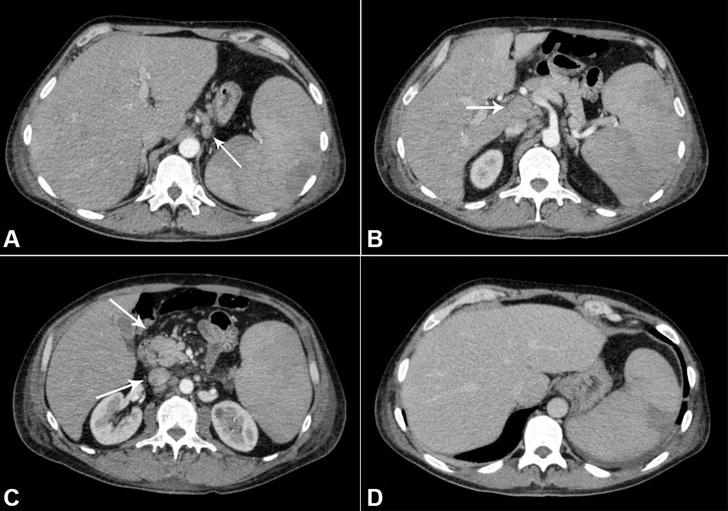

呈现白血病期的弥漫性大B细胞淋巴瘤。

Diffuse large B-cell lymphoma presenting in the leukemic phase.

弥漫性大B细胞淋巴瘤(DLBCL)是最常见的非霍奇金淋巴瘤,由一组组织学和临床行为各异的异质性疾病组成。尽管其他淋巴瘤可能更频繁地出现在白血病期,但这种表现在DLBCL病例中并不常见。诊断淋巴瘤并不总是容易的,患者的临床状况常常会妨碍进行侵入性诊断程序,促使临床医生寻找替代方法以尽可能准确地进行诊断。作者报告了一例中年男性病例,该患者有全身不适、体重减轻和低热病史。外周血细胞计数显示白细胞增多伴原始细胞出现及血小板减少。外周血和骨髓穿刺液的细胞形态学及免疫表型分析,以及骨髓活检并进行全面的免疫组化分析,确诊为白血病期DLBCL。该患者接受了R-CHOP方案治疗,效果良好。由于患者病情危急,避免了进行腹腔淋巴结活检。作者强调了DLBCL这种罕见的表现形式,以及在无法获取淋巴结样本进行诊断检查的情况下,外周血、骨髓穿刺液和骨髓活检相结合用于诊断的方法。